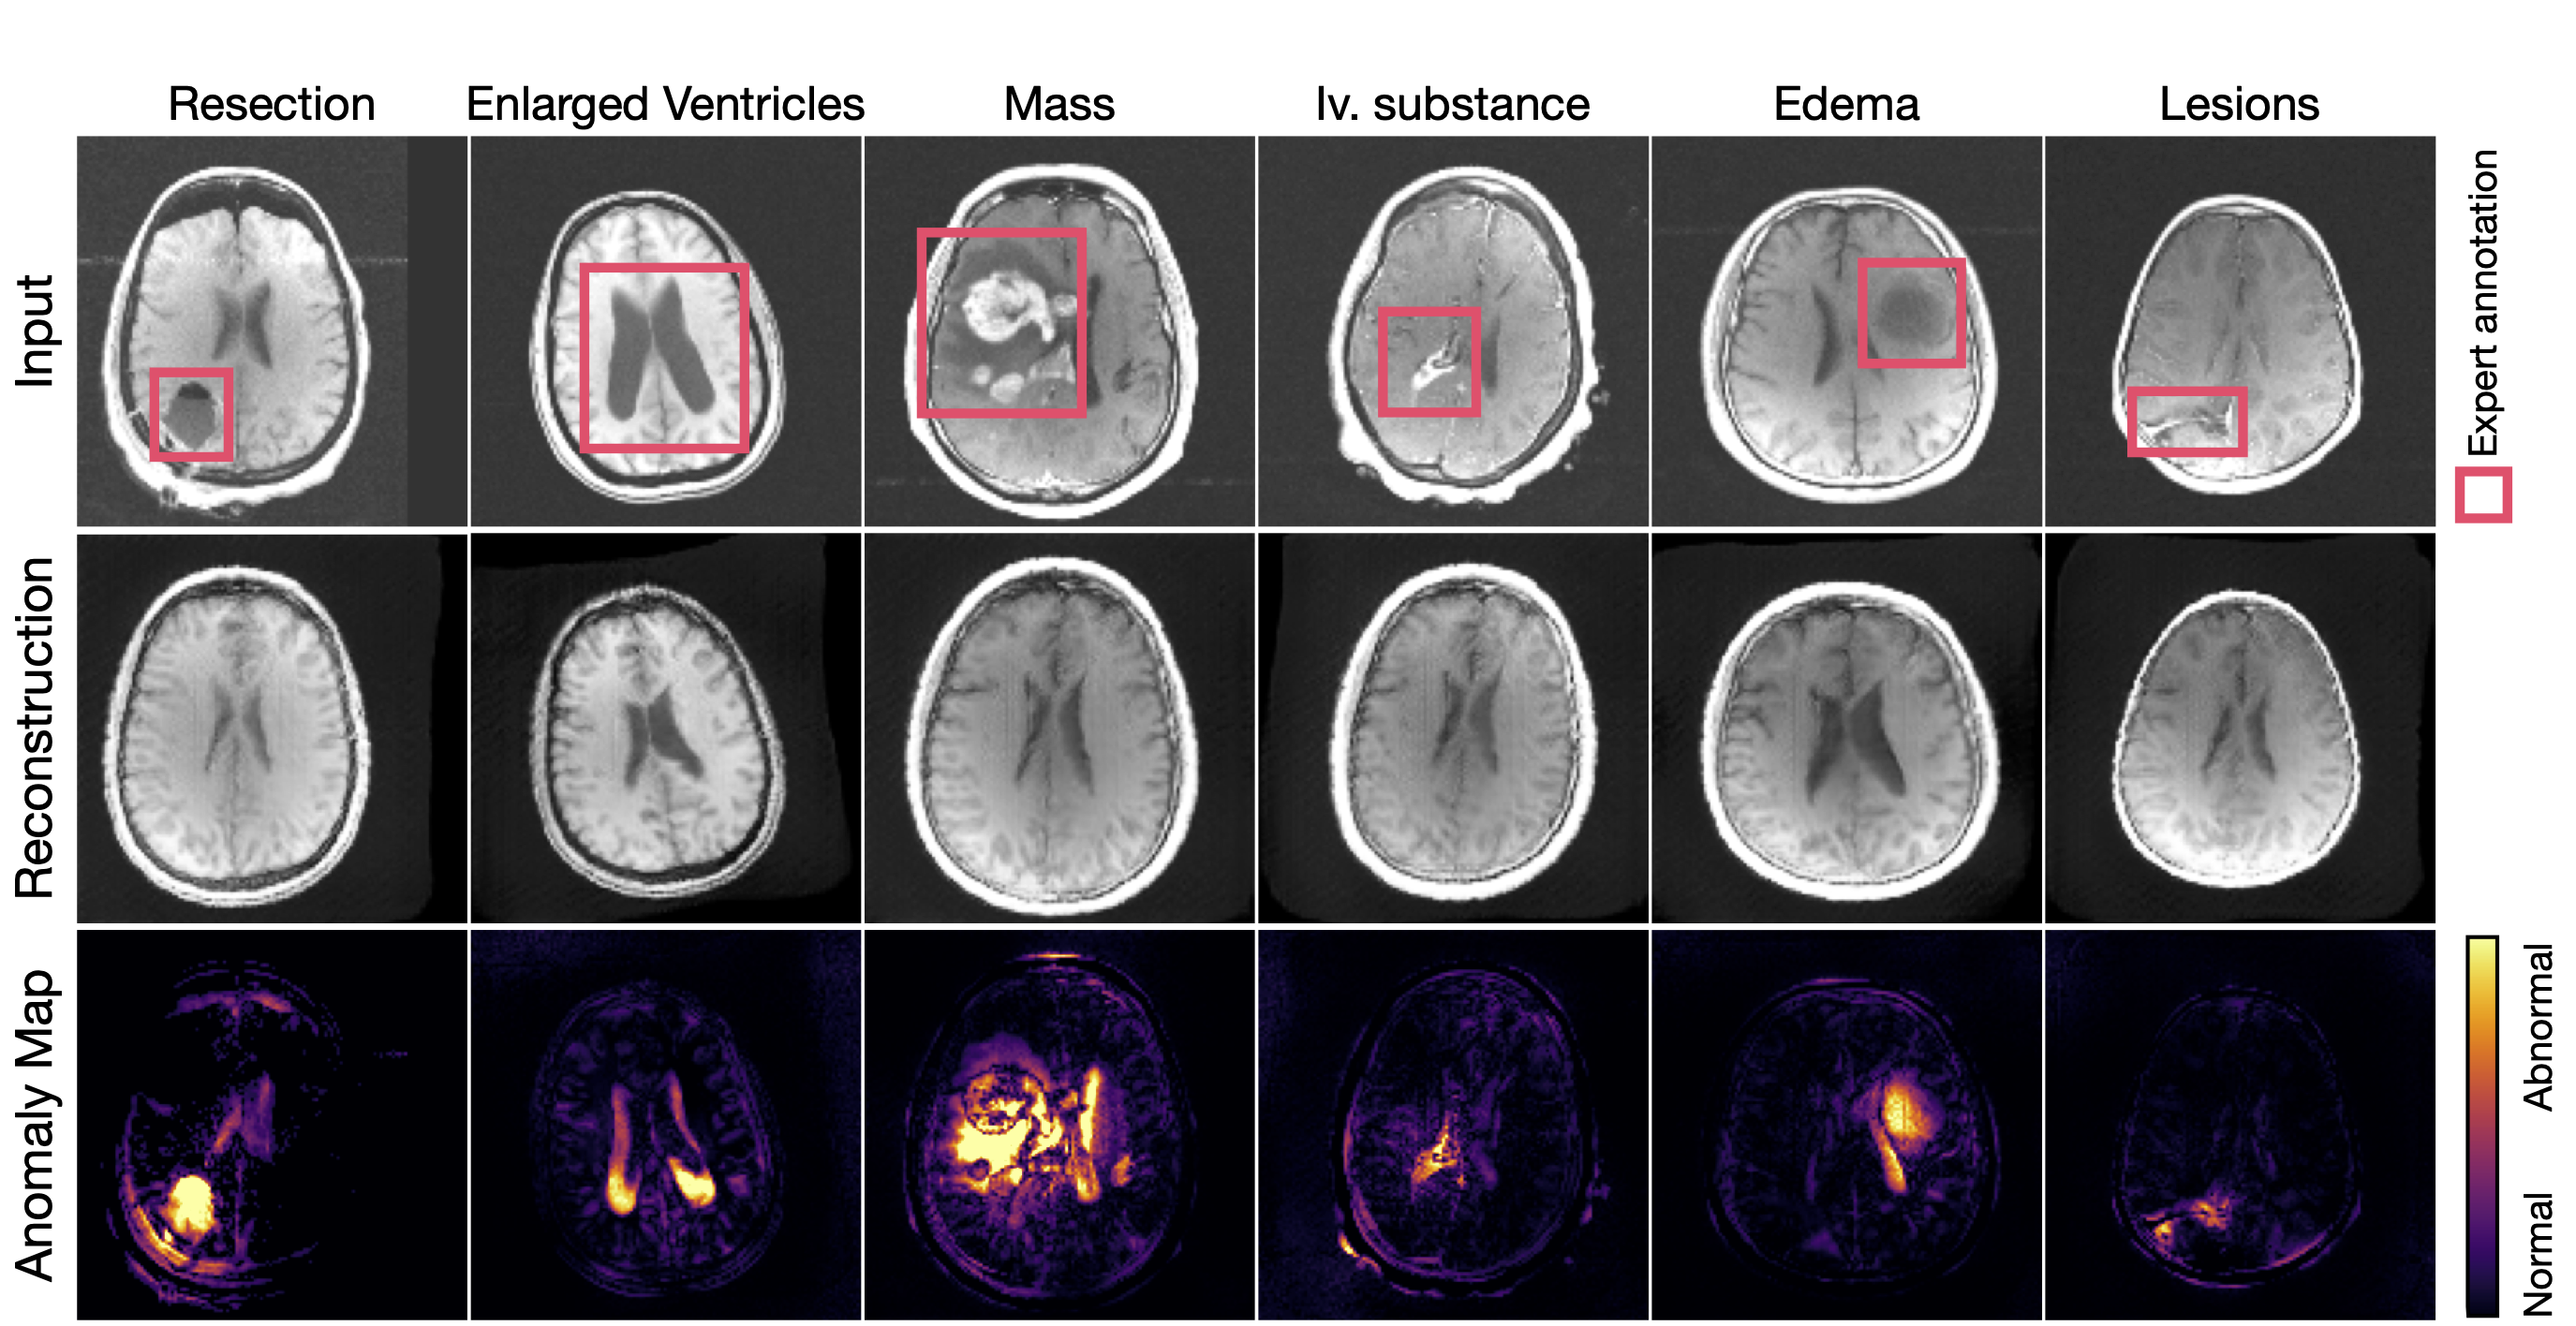

Identifying rare clinical phenotypes and resections without expert labels through OOD detection.

"Unsupervised Anomaly Detection (UAD) is formulated as a label-free approach for open-world clinical settings, where the space of possible pathologies is inherently unbounded, yet is predominantly developed and evaluated under closed-world assumptions tied to known anomaly distributions. We reframe UAD as a problem of generalizing anomaly discovery by grounding detection in principled modeling of the normative anatomical manifold, enabling reliable identification of rare, heterogeneous, and previously unseen disease phenotypes."

Develop representations that remain sensitive to the full pathological spectrum without encoding assumptions about anomaly appearance, prevalence, or intensity.